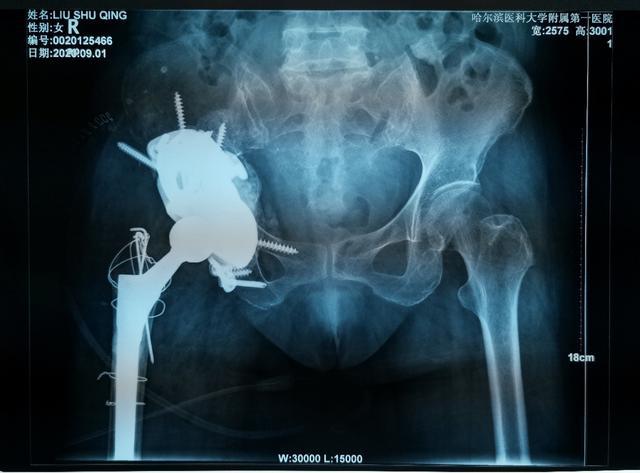

哈醫大一院完成金屬3D打印三翼髖臼假體全髖關節翻修術

對于復雜髖關節翻修多為高齡患者,由于骨缺損巨大、骨質疏松等因素,存在手術難度大、手術費用高等難題。近日,哈醫大一院骨科一病房3D打印團隊,應用3D打印技術,通過術前打印骨骼模型進行模擬假體安裝,成功為一名70歲,全髖關節置換術后15年,髖臼骨缺損巨大,髖臼上部坐骨、髂骨存在巨大空洞型缺損的患者實施了我省首例金屬3D打印三翼髖臼假體(Triflange)+股骨柄假體髖關節翻修術,為患者更換了一個新的、穩定的髖關節。目前患者已康復出院。